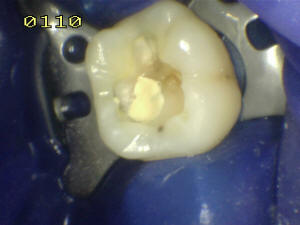

Paciente de 30 años de sexo femenino que concurre a la consulta por perdida de obturaciones en oclusal de 16

Eliminación del tejido cariado en fosa distal

Base de ionómero vitreo en fosa distal

Grabado ácido

Aspecto del esmalte color tiza después del grabado

Adhesivo dental

Obturación en capas de 1 mm de espesor por cada exposición de fotocurado